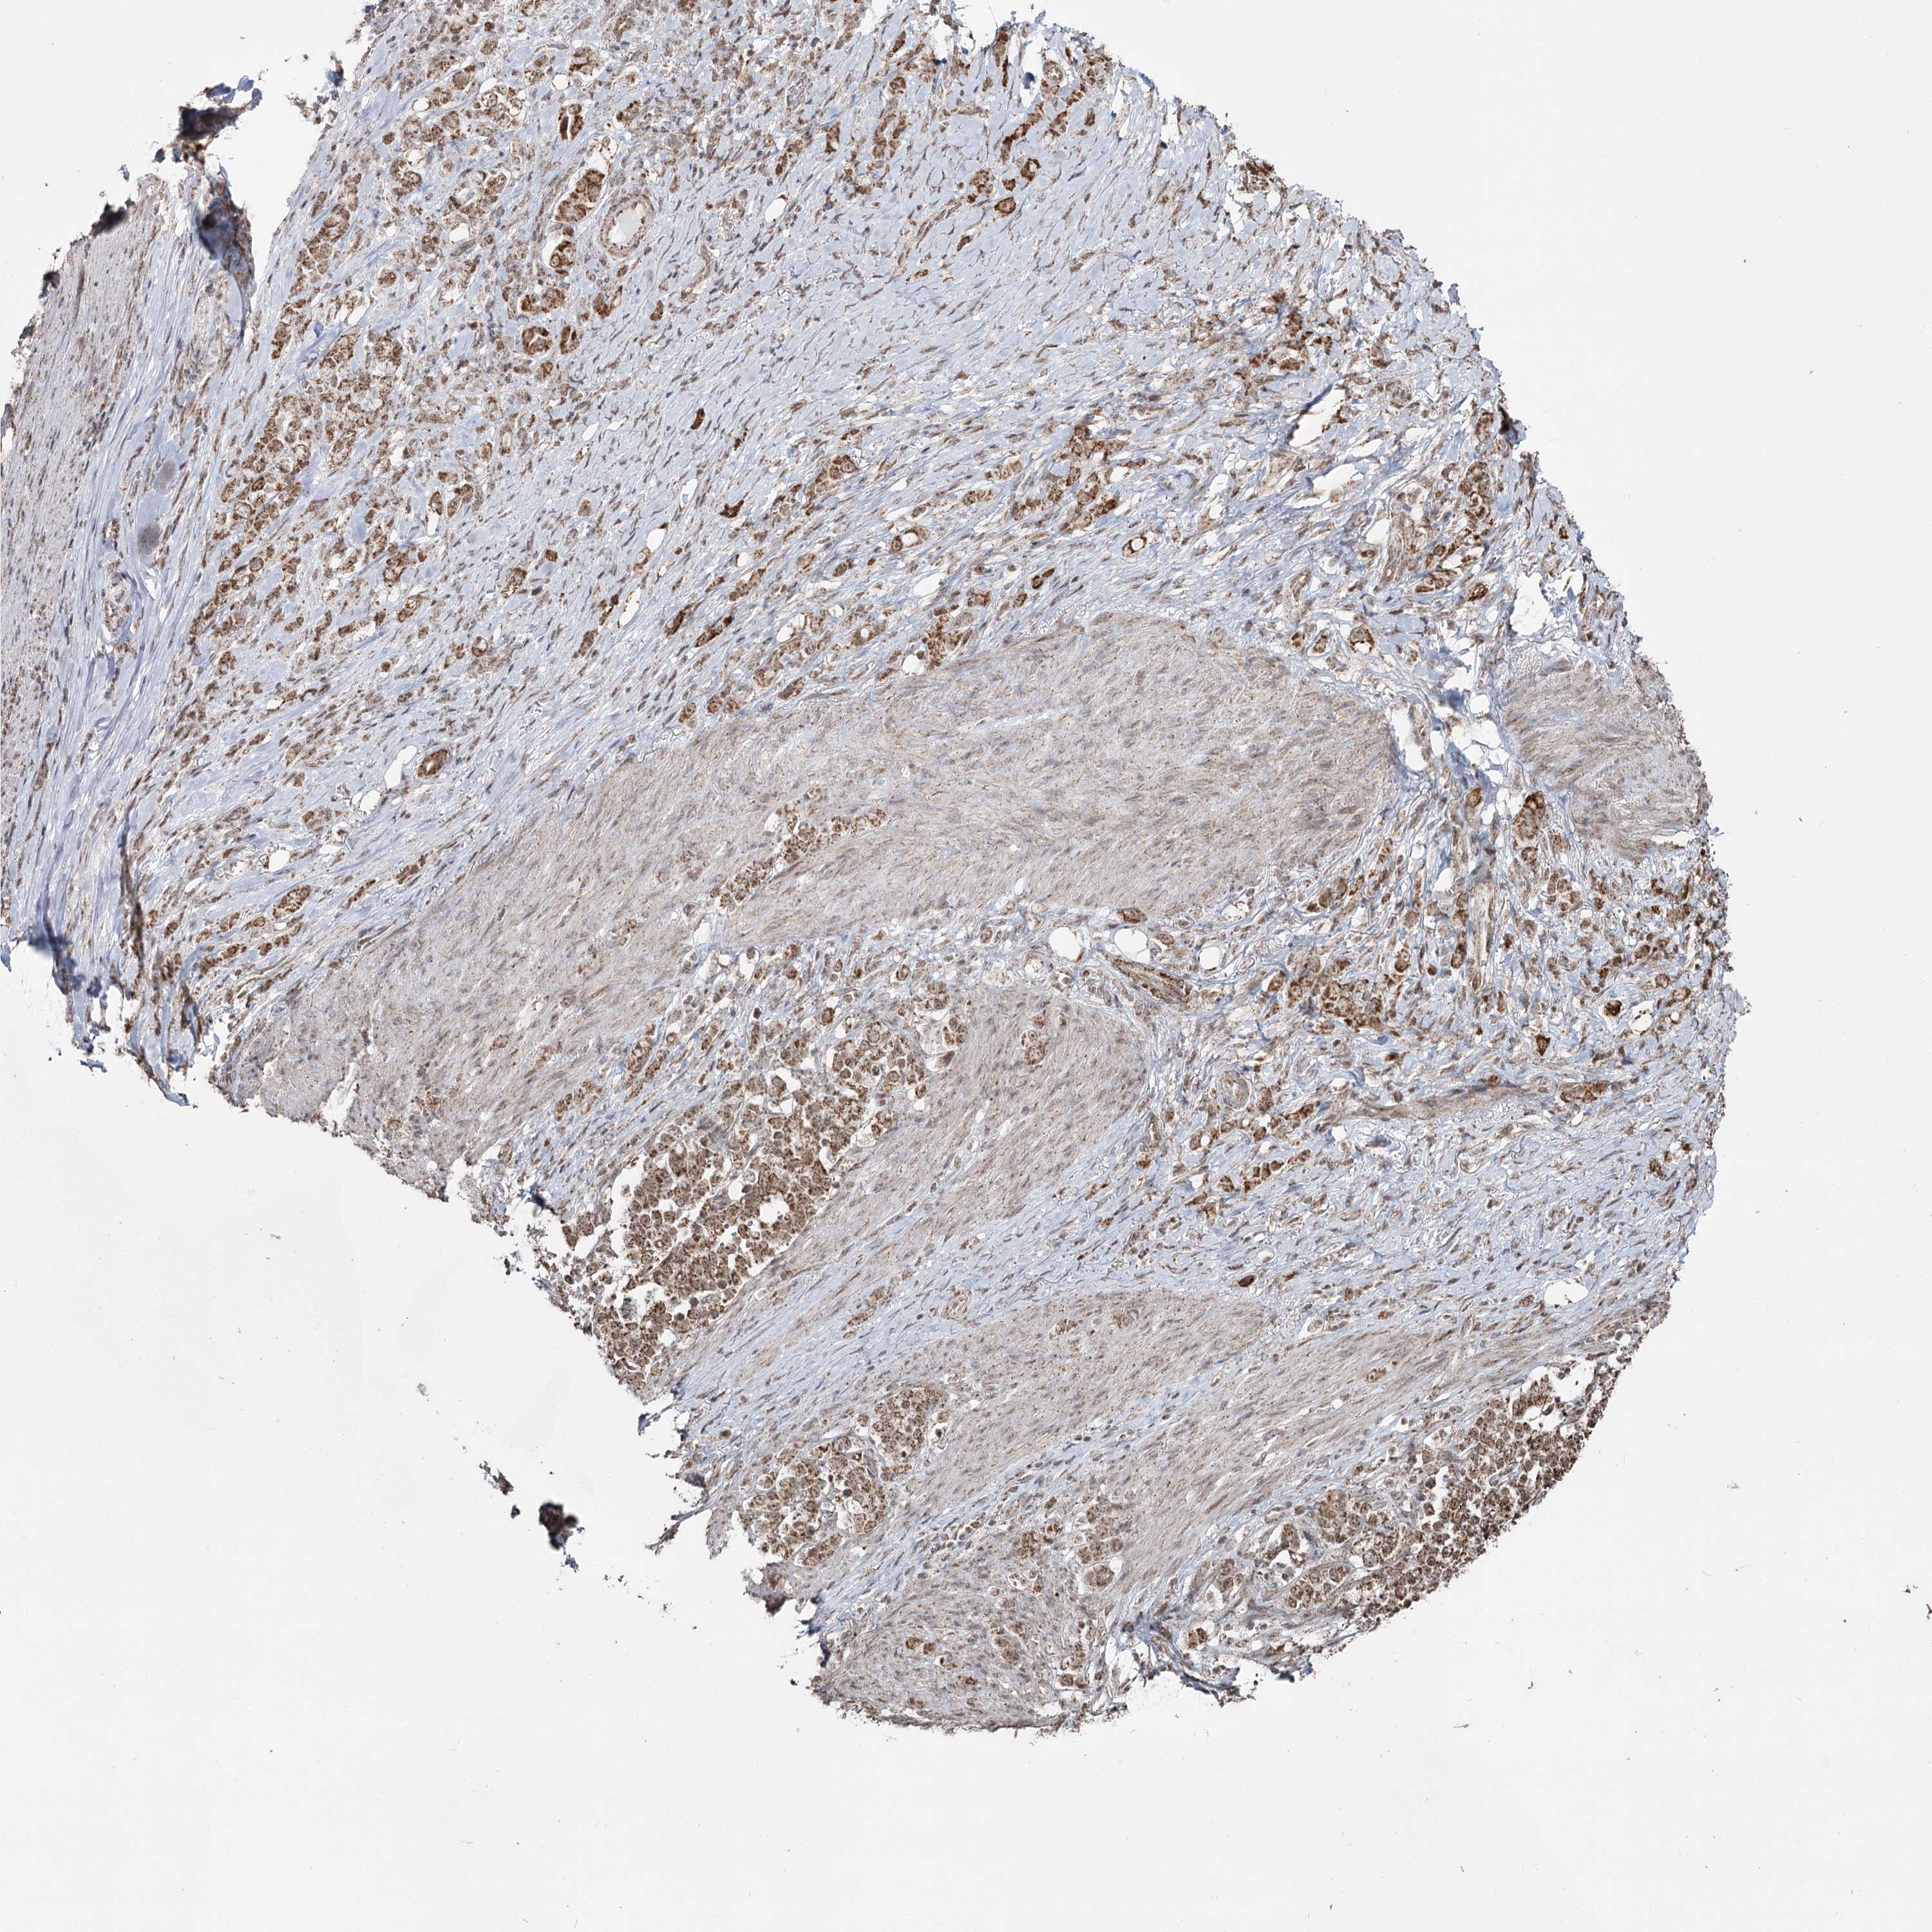

STOMACH CANCER - Protein expressioni

A mouse-over function shows sample information and annotation data. Click on an image to view it in a full screen mode. Samples can be filtered based on level of antibody staining by selecting one or several of the following categories: high, medium, low and not detected. The assay and annotation is described here.

Note that samples used for immunohistochemistry by the Human Protein Atlas do not correspond to samples in the TCGA dataset.

Antibody stainingi

Antibody staining in the annotated cell types in the current human tissue is reported as not detected, low, medium, or high, based on conventional immunohistochemistry profiling in selected tissues. This score is based on the combination of the staining intensity and fraction of stained cells.

Each image is clickable and will lead to virtual microscopy that enables deeper exploration of all samples and also displays staining intensity scores, fraction scores and subcellular localization as well as patient and tissue information for each sample.

Antibody HPA038484

Antibody HPA038485

Staining

High

Medium

Low

Not detected

Intensity

Strong

Moderate

Weak

Negative

Quantity

>75%

75%-25%

<25%

None

Location

Nuclear

Cytoplasmic/membranous

Cytoplasmic/membranous,nuclear

Adenocarcinoma, NOS

Adenocarcinoma, High grade